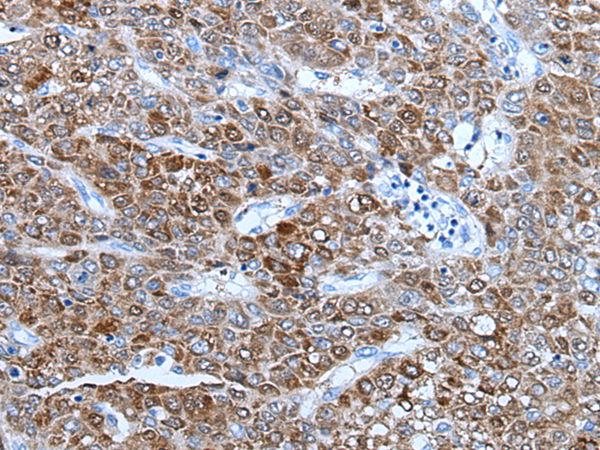

分类: 科研抗体货号: P07217别名: EB1; SCAF1; SCAFI; SIG81; COX7AR; COX7RP应用: WB,IHC反应种属: Human, Mouse